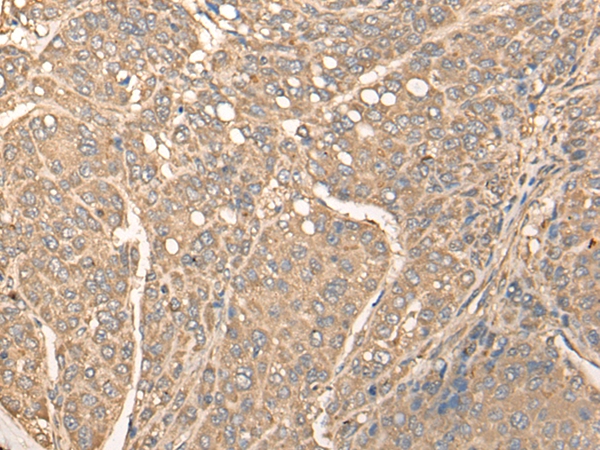

The image on the left is immunohistochemistry of paraffin-embedded Human liver cancer tissue using 46335(BBS1 Antibody) at dilution 1/30, on the right is treated with fusion protein. (Original magnification: x200)